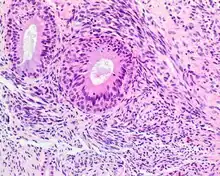

A high-power view of a hematoxylin- and eosin-stained slide showing respiratory epithelial inclusions within a spindled cell neoplasm showing characteristics of a biphenotypic sinonasal sarcoma

Hematoxylin and eosin stained image of a biphenotypic sinonasal sarcoma

• Infiltrative, highly cellular spindled cell neoplasm is poorly circumscribed and unencapsulated. Bone destruction or invasion is common. The cells show medium to long fascicles (nerve fibers), with a herringbone pattern. The cells are remarkably uniform with elongated nuclei. Delicate strands of intercellular collagen without ropy or dense deposition are seen. A very characteristic concurrent surface-type respiratory epithelial proliferation is found from the surface or in small cystic spaces around the cancer cells, often forming glands. The background may have a rich vascularity and usually has a small number of scattered lymphocytes. Extra growths or mitoses are rare, while necrosis, ulceration, and hemorrhage are usually absent.